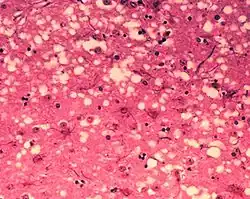

D'un point de vue anatomopathologique, on observe ainsi au niveau de l'encéphale la formation de vacuoles (donnant un aspect spongieux au cerveau, d'où le nom de spongiforme dans ESST), une mort des neurones, une gliose (multiplication des astrocytes et de la microglie) et l'accumulation d'une protéine de l'hôte, la PrPC (abréviation de protéine prion cellulaire, l'isoforme normale), sous une conformation anormale (ou mal repliée) alors dénommée PrPSc (abréviation de protéine prion de la scrapie)[6].

- La mise en évidence d'une triade de signes neuropathologiques (perte neuronale, astrogliose, vacuoles spongiformes) ;